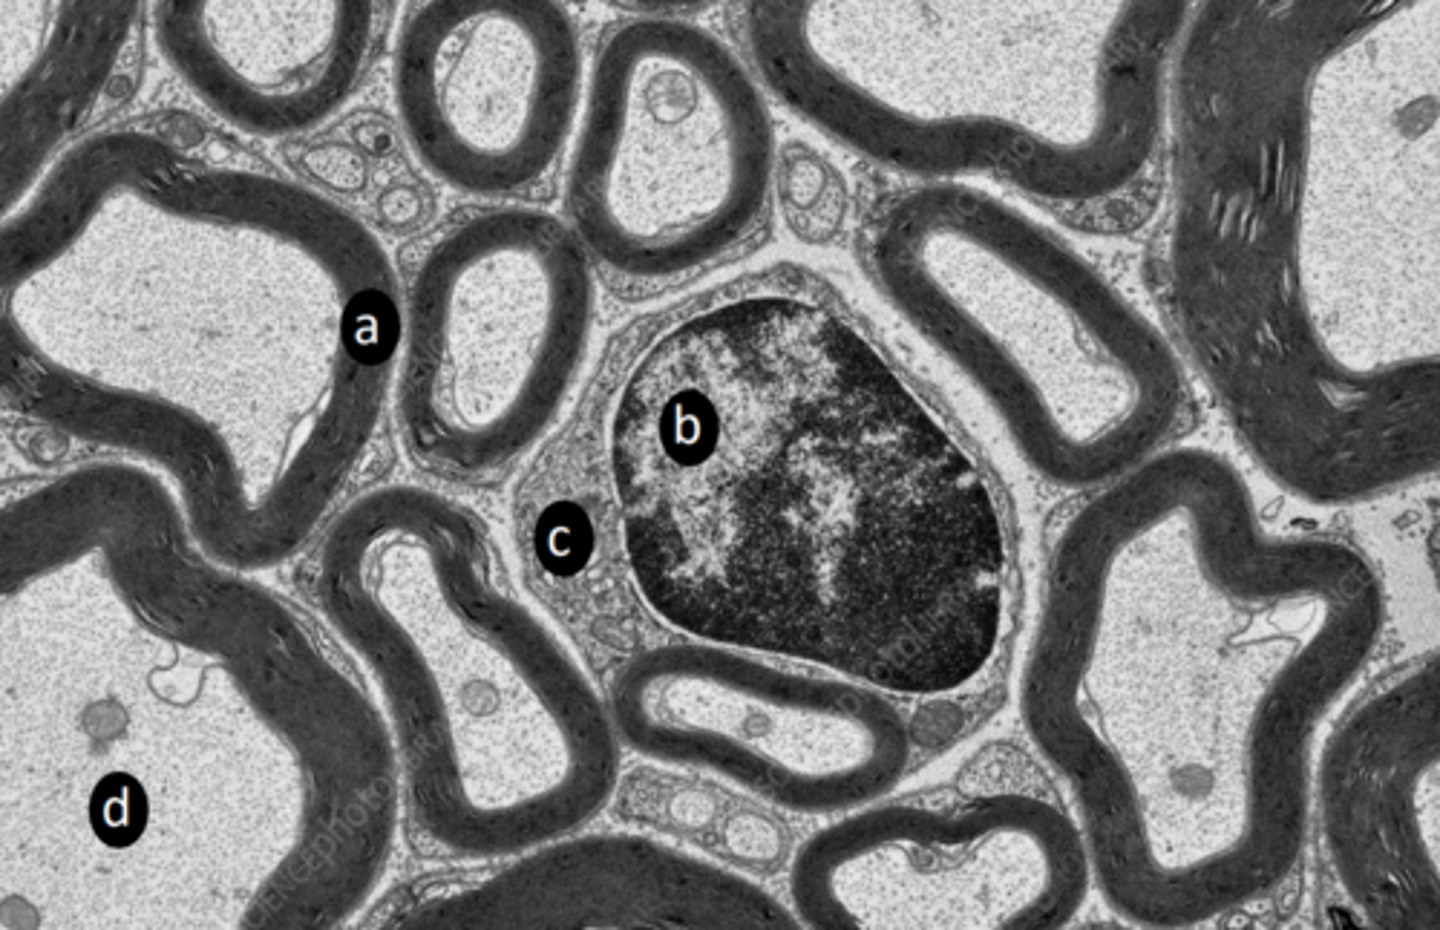

myelin sheath

a: structure

<p>a: structure</p>

schwann cell nucleus

b: structure

<p>b: structure</p>

schwann cell cytoplasm

c: structure

<p>c: structure</p>

microtubule, neurofilament, mitochondria

d: two structures present in labelled region

<p>d: two structures present in labelled region</p>